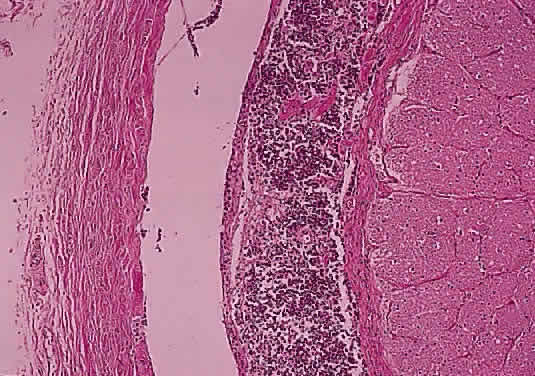

Injury to the retina or any peripheral portion of the optic nerve results in rapid ascending atrophy of the central portion. Initially, the axons at the peripheral portion swell. Retrograde degeneration of the axon then occurs, with loss of retinal ganglion cells. Clinically, there is pallor of the optic disc (Fig. 27), and early decreased fluorescence is seen with angiography. The atrophic optic nerve is surrounded by a loose sheath (Fig. 28). Microscopically, there is shrinkage of the nerve parenchyma secondary to axonal and myelin loss and gliosis (Fig. 29). Corpora amylacea accumulate in the subpial and perivascular areas (Fig. 30). With shrinkage of the nerve, the subarachnoid space is widened and the pial strands and arteriolar walls are thickened. Atrophy that is secondary to glaucoma is initially seen in the prelaminar region. Loss of astrocytes and axons results in baring of the lamina and deep excavation of the optic cup (Figs. 31 and 32).

Fig. 27. Fundus appearance of optic atrophy.

Fig. 29. Thick collagenous pial strands in atrophic optic nerve extend around central vessels (cross-section hematoxylin and eosin staining).